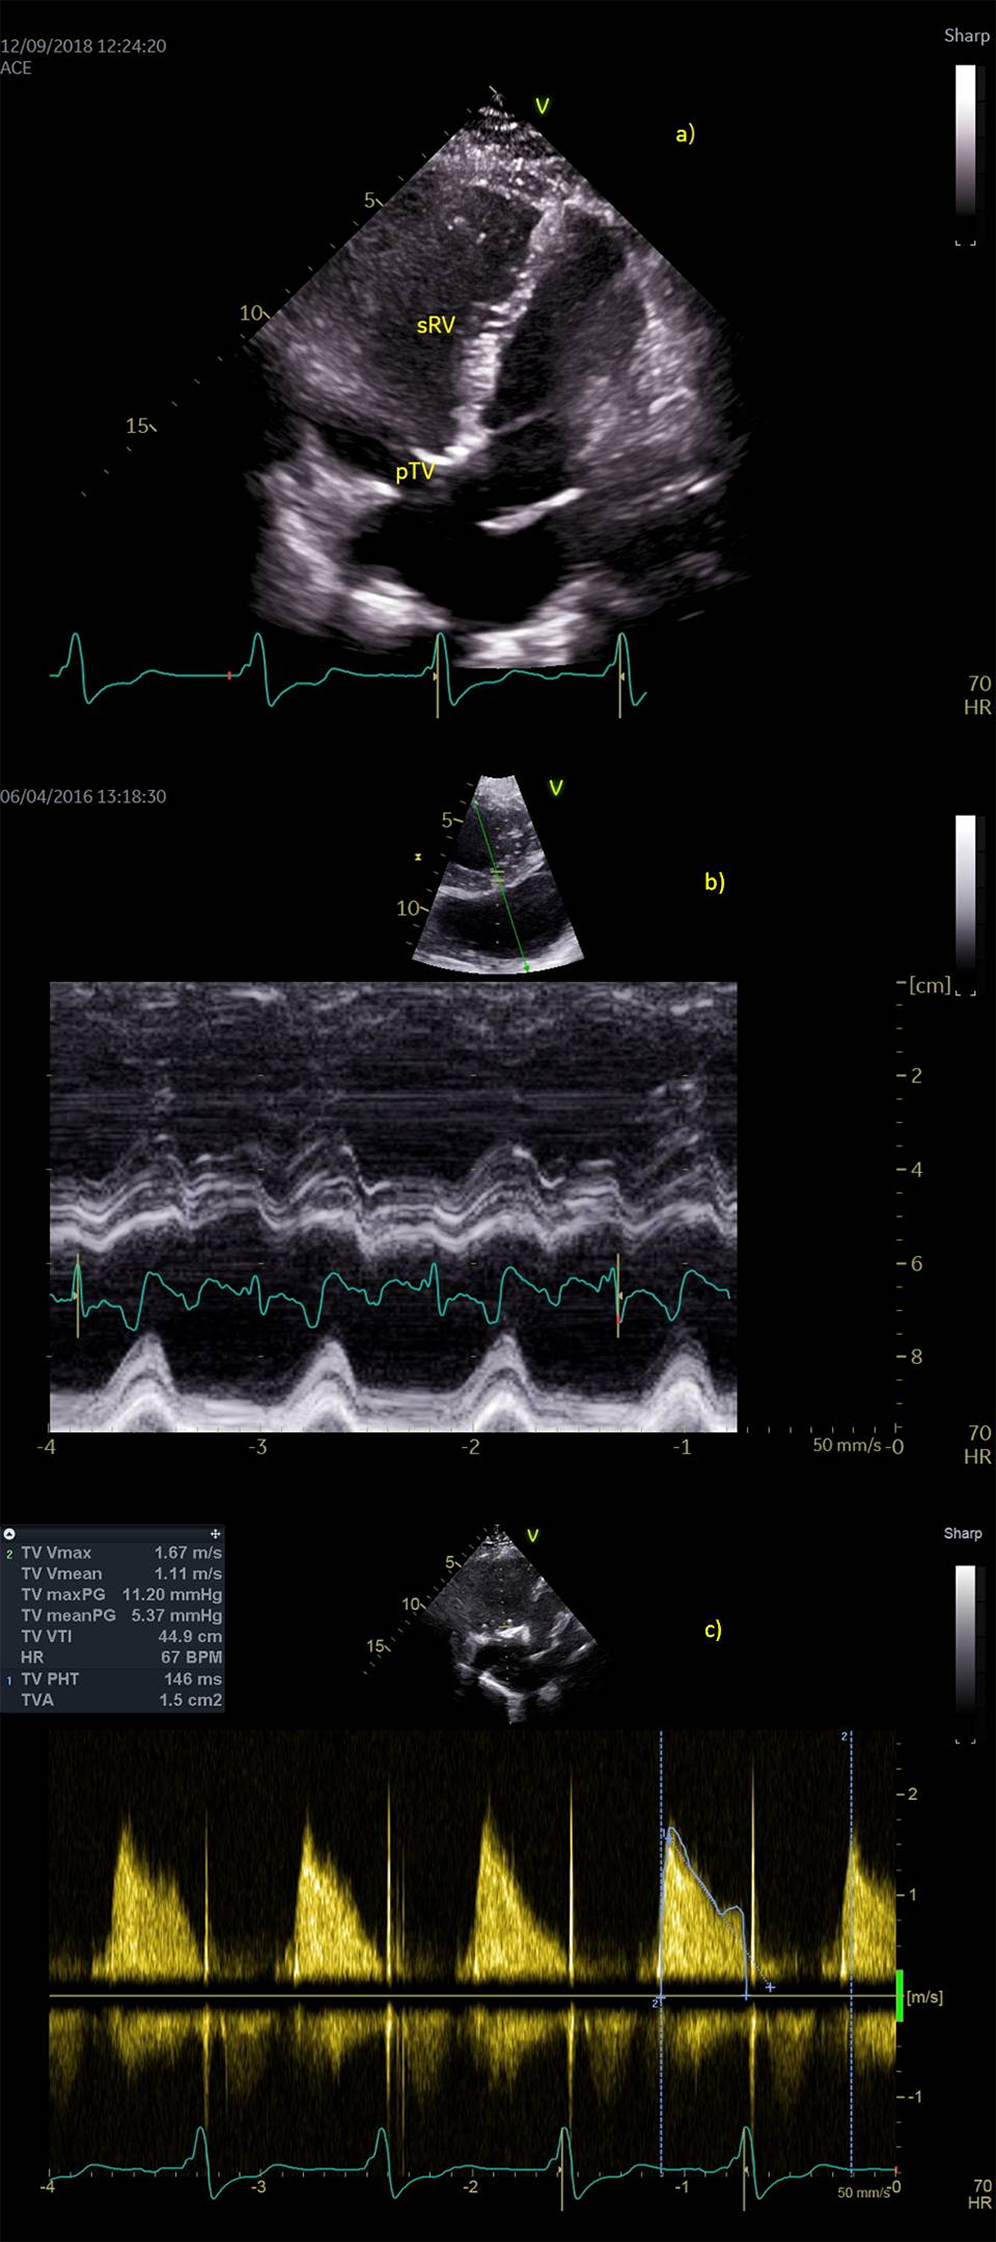

We present a case of a 33-year-old female patient (written informed consent was signed by the patient) with TGA, treated with septostomy by Rashkind a few days after her birth and by the Senning procedure at the age of nine months. She was presented in our clinic with palpitations and dyspnea in 2011, at the age of 26. At that moment she was hemodynamically stabile, tachycardic 106/min with a systolic heart murmur (3/6) and no clinical signs of congestion. Auscultation of the lung revealed no signs of congestion and no peripheral edema was present. Auscultation of the lung revealed no signs of congestion and no peripheral edema was present. Monitoring electrocardiogram (ECG) showed a continuous atrial undulation (UA) and wide QRS, so antiarrhythmic therapy with bisoprolol and amiodarone was started. Beside the arrhythmia, echocardiographic examination (ECHO) revealed a dilated sRV with end-diastolic volume (EDV RV) of 220 ml (126 ml/m2), moderate sTR due to combined functional regurgitation with primary valve lesion-prolapse of posterior leaflet, and reduced EF of sRV 42%. Due to drug- and electrocardioversion resistant arrhythmia a successful radiofrequency ablation of the re-entry tachycardia was performed in December 2012. During the next four months of follow up the patient was clinically compensated, in New York Heart Association (NYHA) I functional status, with no change in effort tolerance. Control ECG monitoring in March 2013 revealed recurrence of UA while control ECHO verified a worsening of sTR (regurgitation volume > 50% of the stroke volume) to severe regurgitation and moderate reduction of sRV systolic function. Pulmonary artery pressure was not elevated. Due to a resistant and long-lasting UA, systolic function of sRV progressively declined implicating a component of tachycardia induced cardiomyopathy, followed by an increased regurgitation volume of sTR (Figs. 1a–1c). Gadolinium scan (magnetic resonance) of sRV showed a dilated systemic right atrium, dilated and hypertrophied sRV (EDV 161 ml, 92 ml/m2, end-systolic volume (ESV) 83 ml, stroke volume (SV) 78 ml, EF 48%), thin left ventricle (LV) walls (EDV 76 ml, ESV 30 ml, SV 46 ml, EF 60%), no regional contractility abnormalities and no signs of replacement fibrosis. Coronary stenosis was ruled out by coronary angiography. Native ECG showed RBBB with QRS width 140 ms. The patient was scheduled for sTV replacement and AV node ablation to be followed by implantation of pacemaker. During the surgery, a biological TV prothesis (pTV) (Edwards Lifesciences C-E Perimount Magma Mitral 33 mm) was implanted and AV node ablation was performed. In order to prevent mechanical iatrogenic dysynchrony of permanent pacing, a CRT with biventricular pacing was implanted during surgery, placing epicardial bipolar leads (Medtronic Model 4968, atrial lead on sRV and ventricular lead on LV in DVIR pacing mode, with AV delay of 30 ms). The optimization of lead placement was guided using transesophageal echocardiography in order to find the most favorable stimulation sites on the right and left ventricular walls that would achieve the most synchronous sRV contraction. An echocardiographic control (April 2013) revealed a positive remodelling of sRV based on reduction of EDV RV to 60 ml, an increase in EF RV 60% and synchronous myocardial contractions (Figs. 2a–2c) and QRS 130 ms. The CRT memory follow up data showed no arrhythmias, so betablockers could be discontinued and the risks during pregnancy decreased to an acceptable level. Nineteen months later an ovarium dermoid cyst removal and correction of septate uterus was performed. Three years after the surgery, the patient was in NYHA Class I, with normal sRV size and function and synchronous myocardial contractions (Fig. 2). The underlying atrial rhythm was UA. The patient was diagnosed with hereditary thrombophilia. Despite increased risk of cardiovascular events, our patient had a strong motivation and an increasing wish to become a mother that we approved. After several attempts of unsuccessful in vitro fertilization procedures, a twin pregnancy was achieved. In the 30th week of gestation, in July 2017, no clinical signs of heart failure (HF) were present but ECHO revealed a slight dilatation and worsening od EF of sRV and sTR (EDV 140 ml, ESV 70 ml, EF 45%). Despite the suggested restriction of physical exertion and bed rest in the following gestational weeks, an excessive volume overload and further dilatation of sRV were noticed.

Figure 2: Postoperative echocardiography. a) Apical four-chamber view shows complete positive remodeling of systemic right ventricle (sRV), b) Synchronous contraction of the sRV walls (anatomic M mode of the short axis view, arrow points to systolic contraction of sRV) c) normal continuous Doppler trace across biological prosthesis at tricuspid place (pTV)